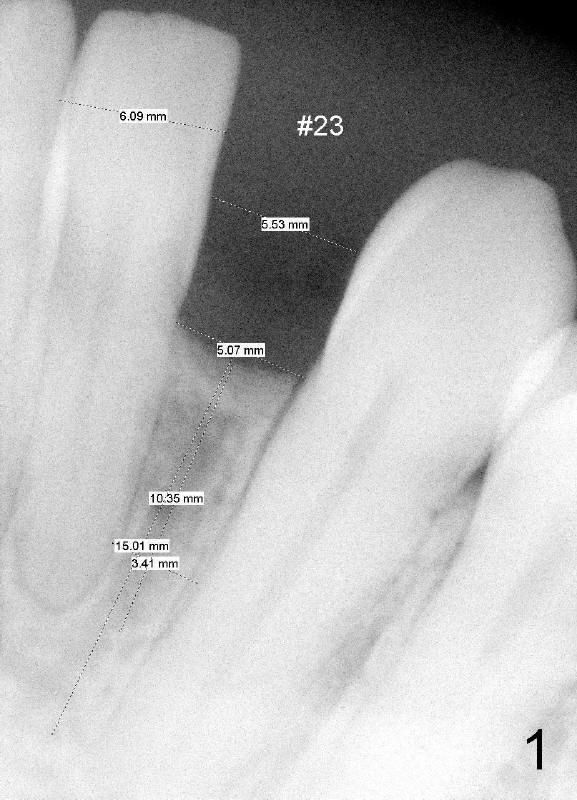

A 44-year-old black lady with ortho several years ago requests fixed restoration for #23 with narrow mesiodistal width (Fig.1). Treatment options are proposed: fixed prosthetic denture and implant. After discussion of advantages and disadvantages of each option, the patient agrees to have implant restoration. A 1.5 mm pilot drill is used to create osteotomy (Fig.2,3). After using 2.0 mm and 3.0 mm tapered osteotomes through the cortex at the crest, 3x17 mm 1-piece implant is placed (Fig.4) and temporary crown is immediately cemented with no centric or lateral occlusion. The patient is doing fine postop, although there is very mild percussion involving the tooth #24, three days postop. Fig.5 and 6 show that the temporary crown is bonded to the neighboring teeth interproximally and lingually. Retrospectively, ortho should have been done to torque the root of the tooth #22 prior to implant placement. Fig.3,4 show that there is space between #21 and 22.